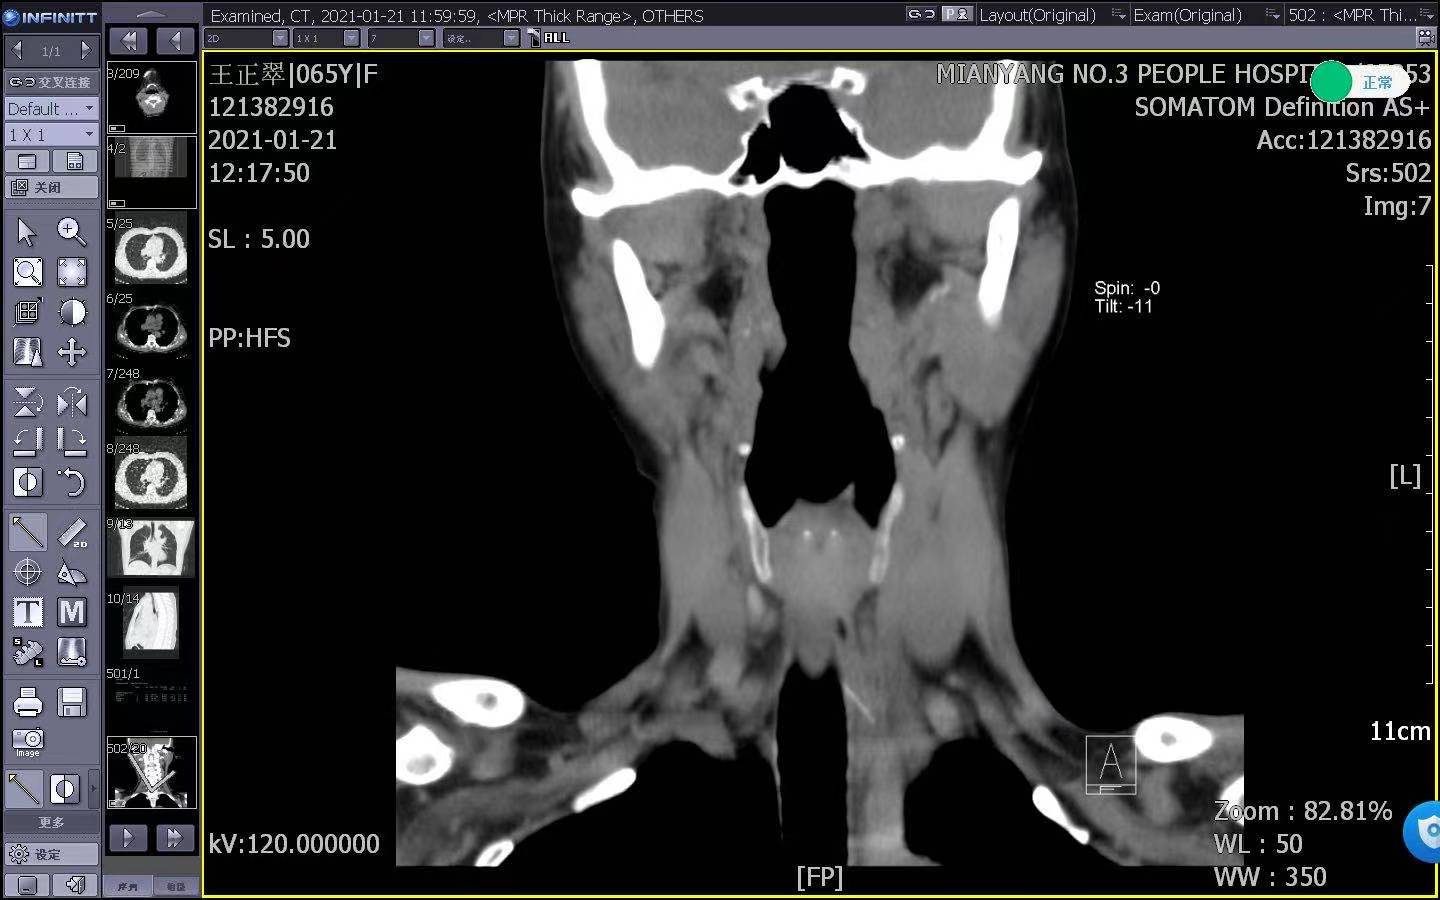

• 甲状腺头颈颌面外科开展高难度双侧下颌骨髁突囊内骨折手术

甲状腺头颈颌面外科开展高难度双侧下颌骨髁突囊内骨折手术 2021-03-29 下颌骨髁突是下颌骨的下颌支末端有两个突起,位于后方的称之为髁突,构成颞颌关节,是面部唯一可以活动的骨头。人类的进食、言语等重要功能,与它息息相关,同时也是下颌骨最脆弱的地方之一,容易因外伤导致骨折。前段时间,16岁的小张在学校上体育课时不慎摔伤,出现耳前区肿…